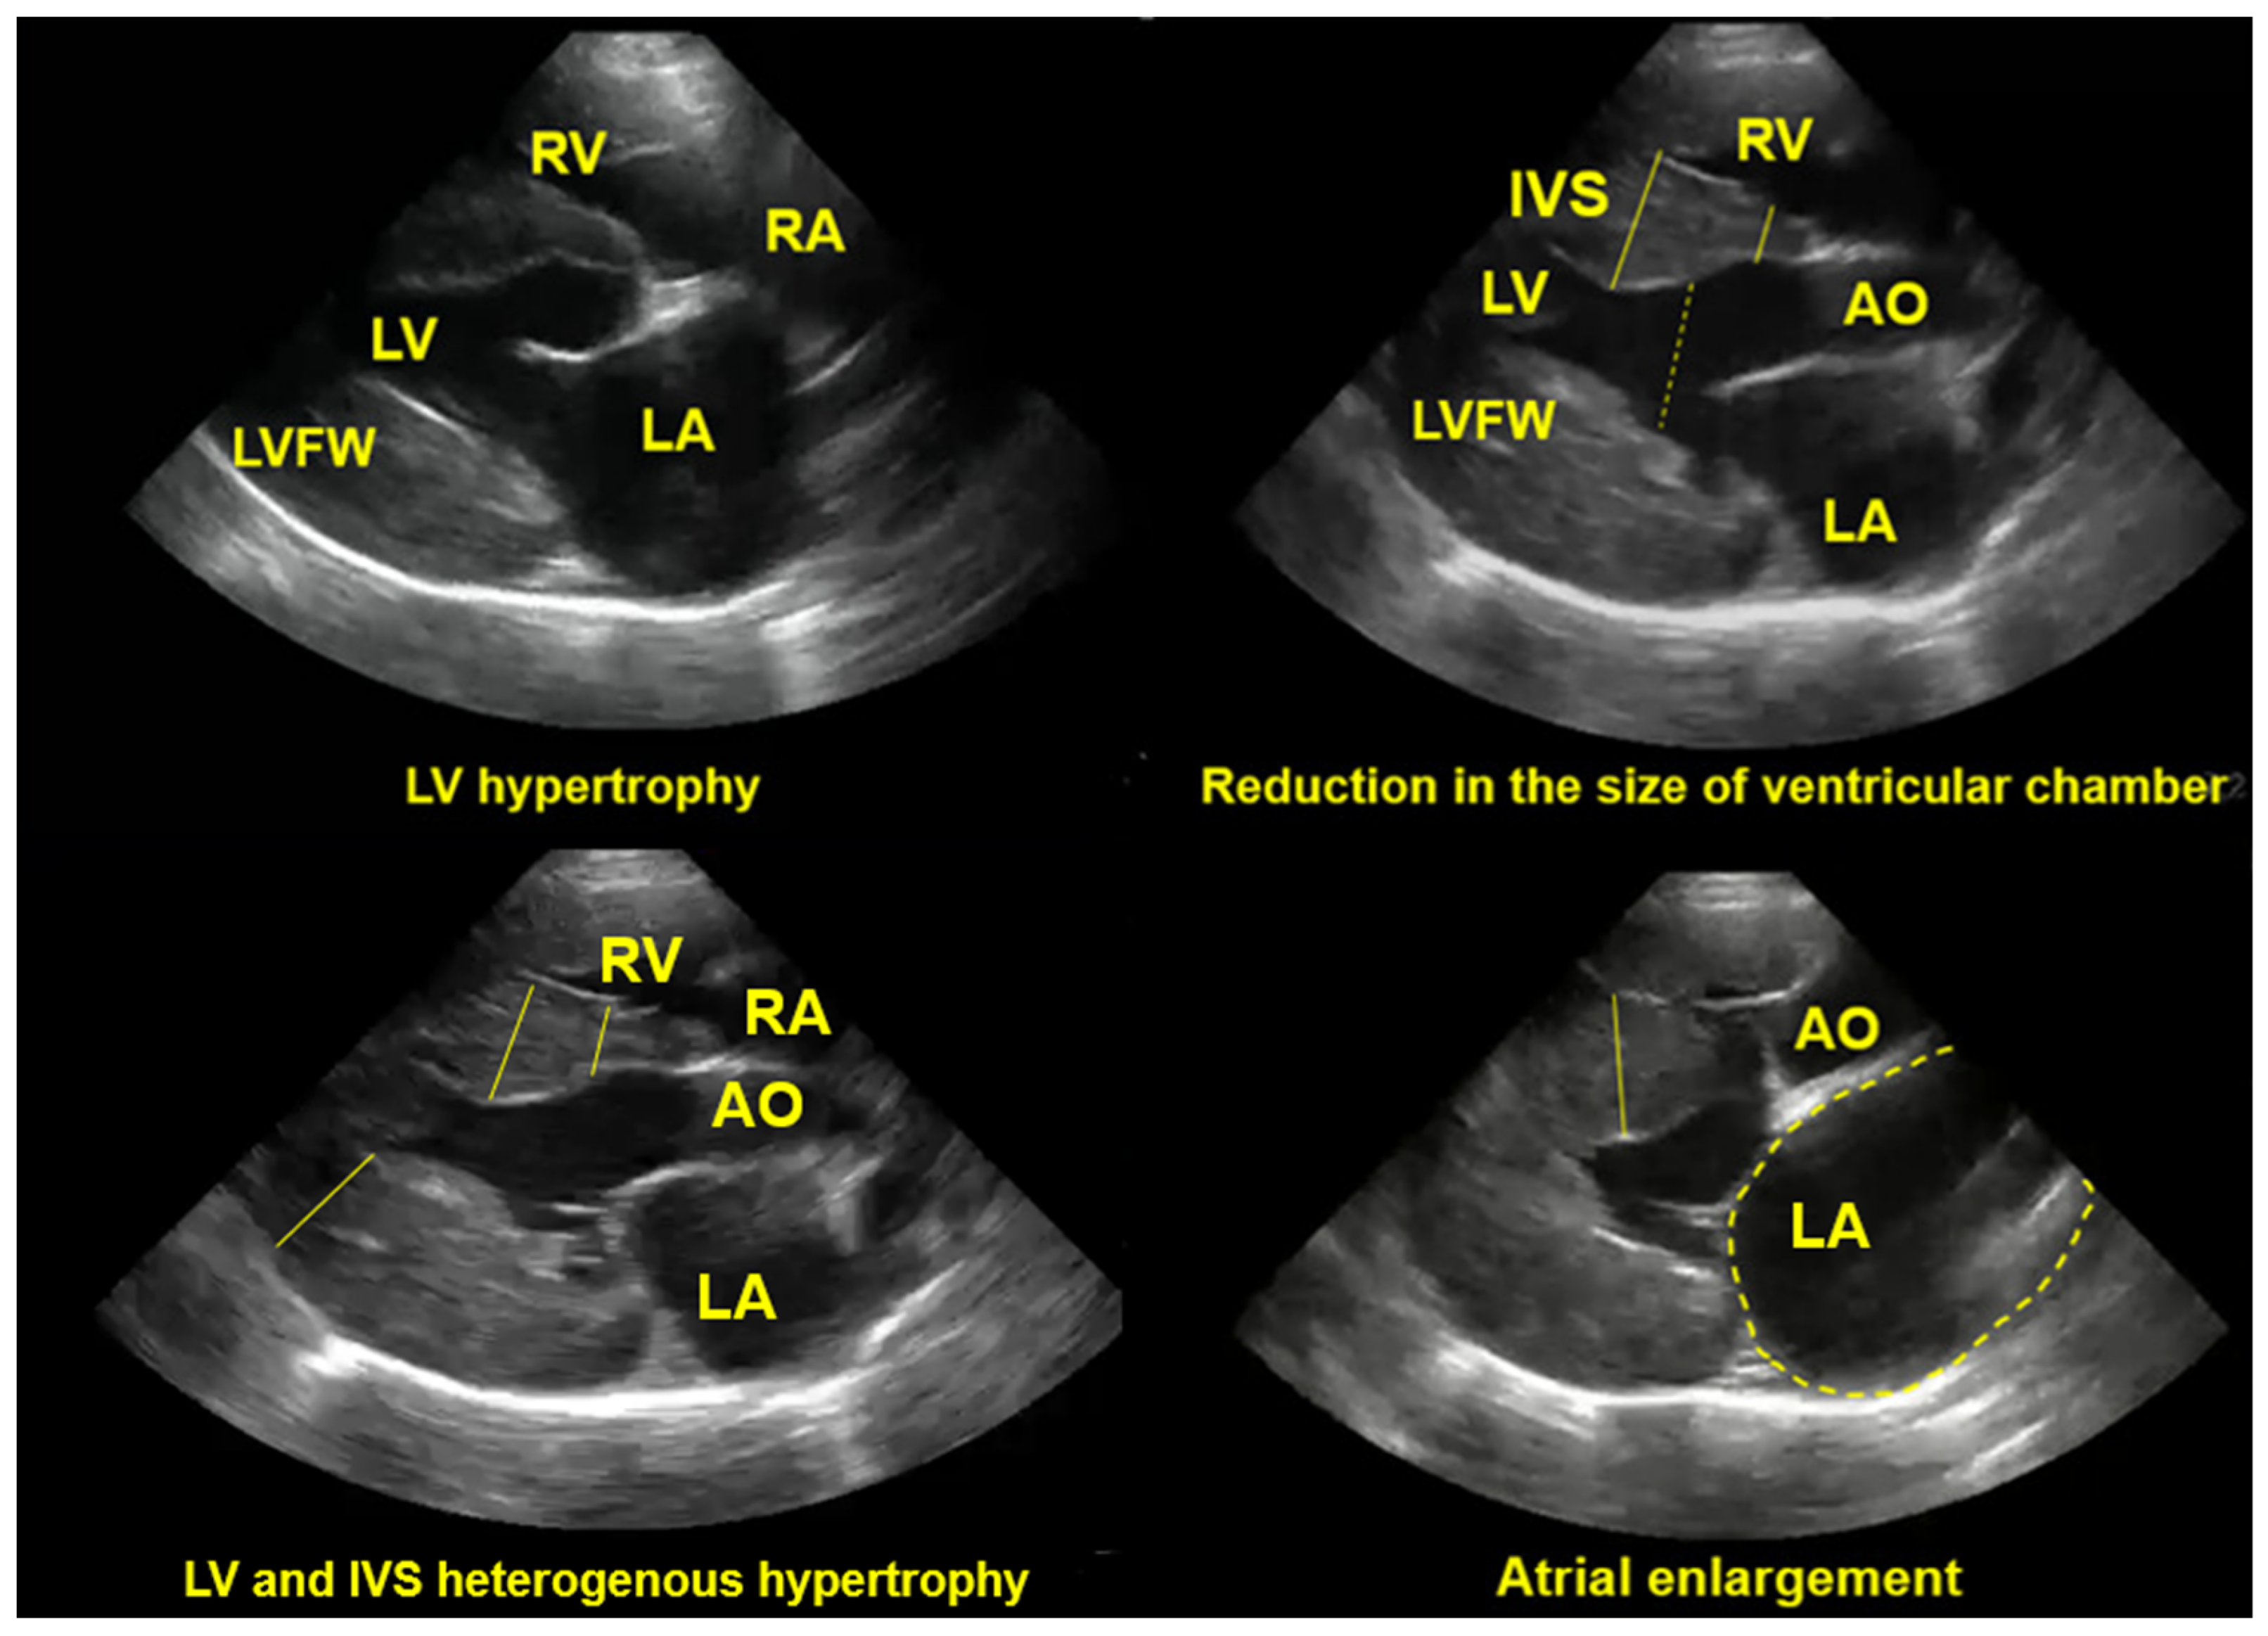

7.2.3. Echocardiography

- Häggström, J.; Fuentes, L.V.; Wess, G. Screening for hypertrophic cardiomyopathy in cats. J. Vet. Cardiol. 2015, 17, 134–149. [Google Scholar] [CrossRef]

- Parato, V.M.; Antoncecchi, V.; Sozzi, F.; Marazia, S.; Zito, A.; Maiello, M.; Palmiero, P.; ISCU. Echocardiographic diagnosis of the different phenotypes of hypertrophic cardiomyopathy. Cardiovasc. Ultrasound. 2016, 14, 30. [Google Scholar] [CrossRef] [PubMed]